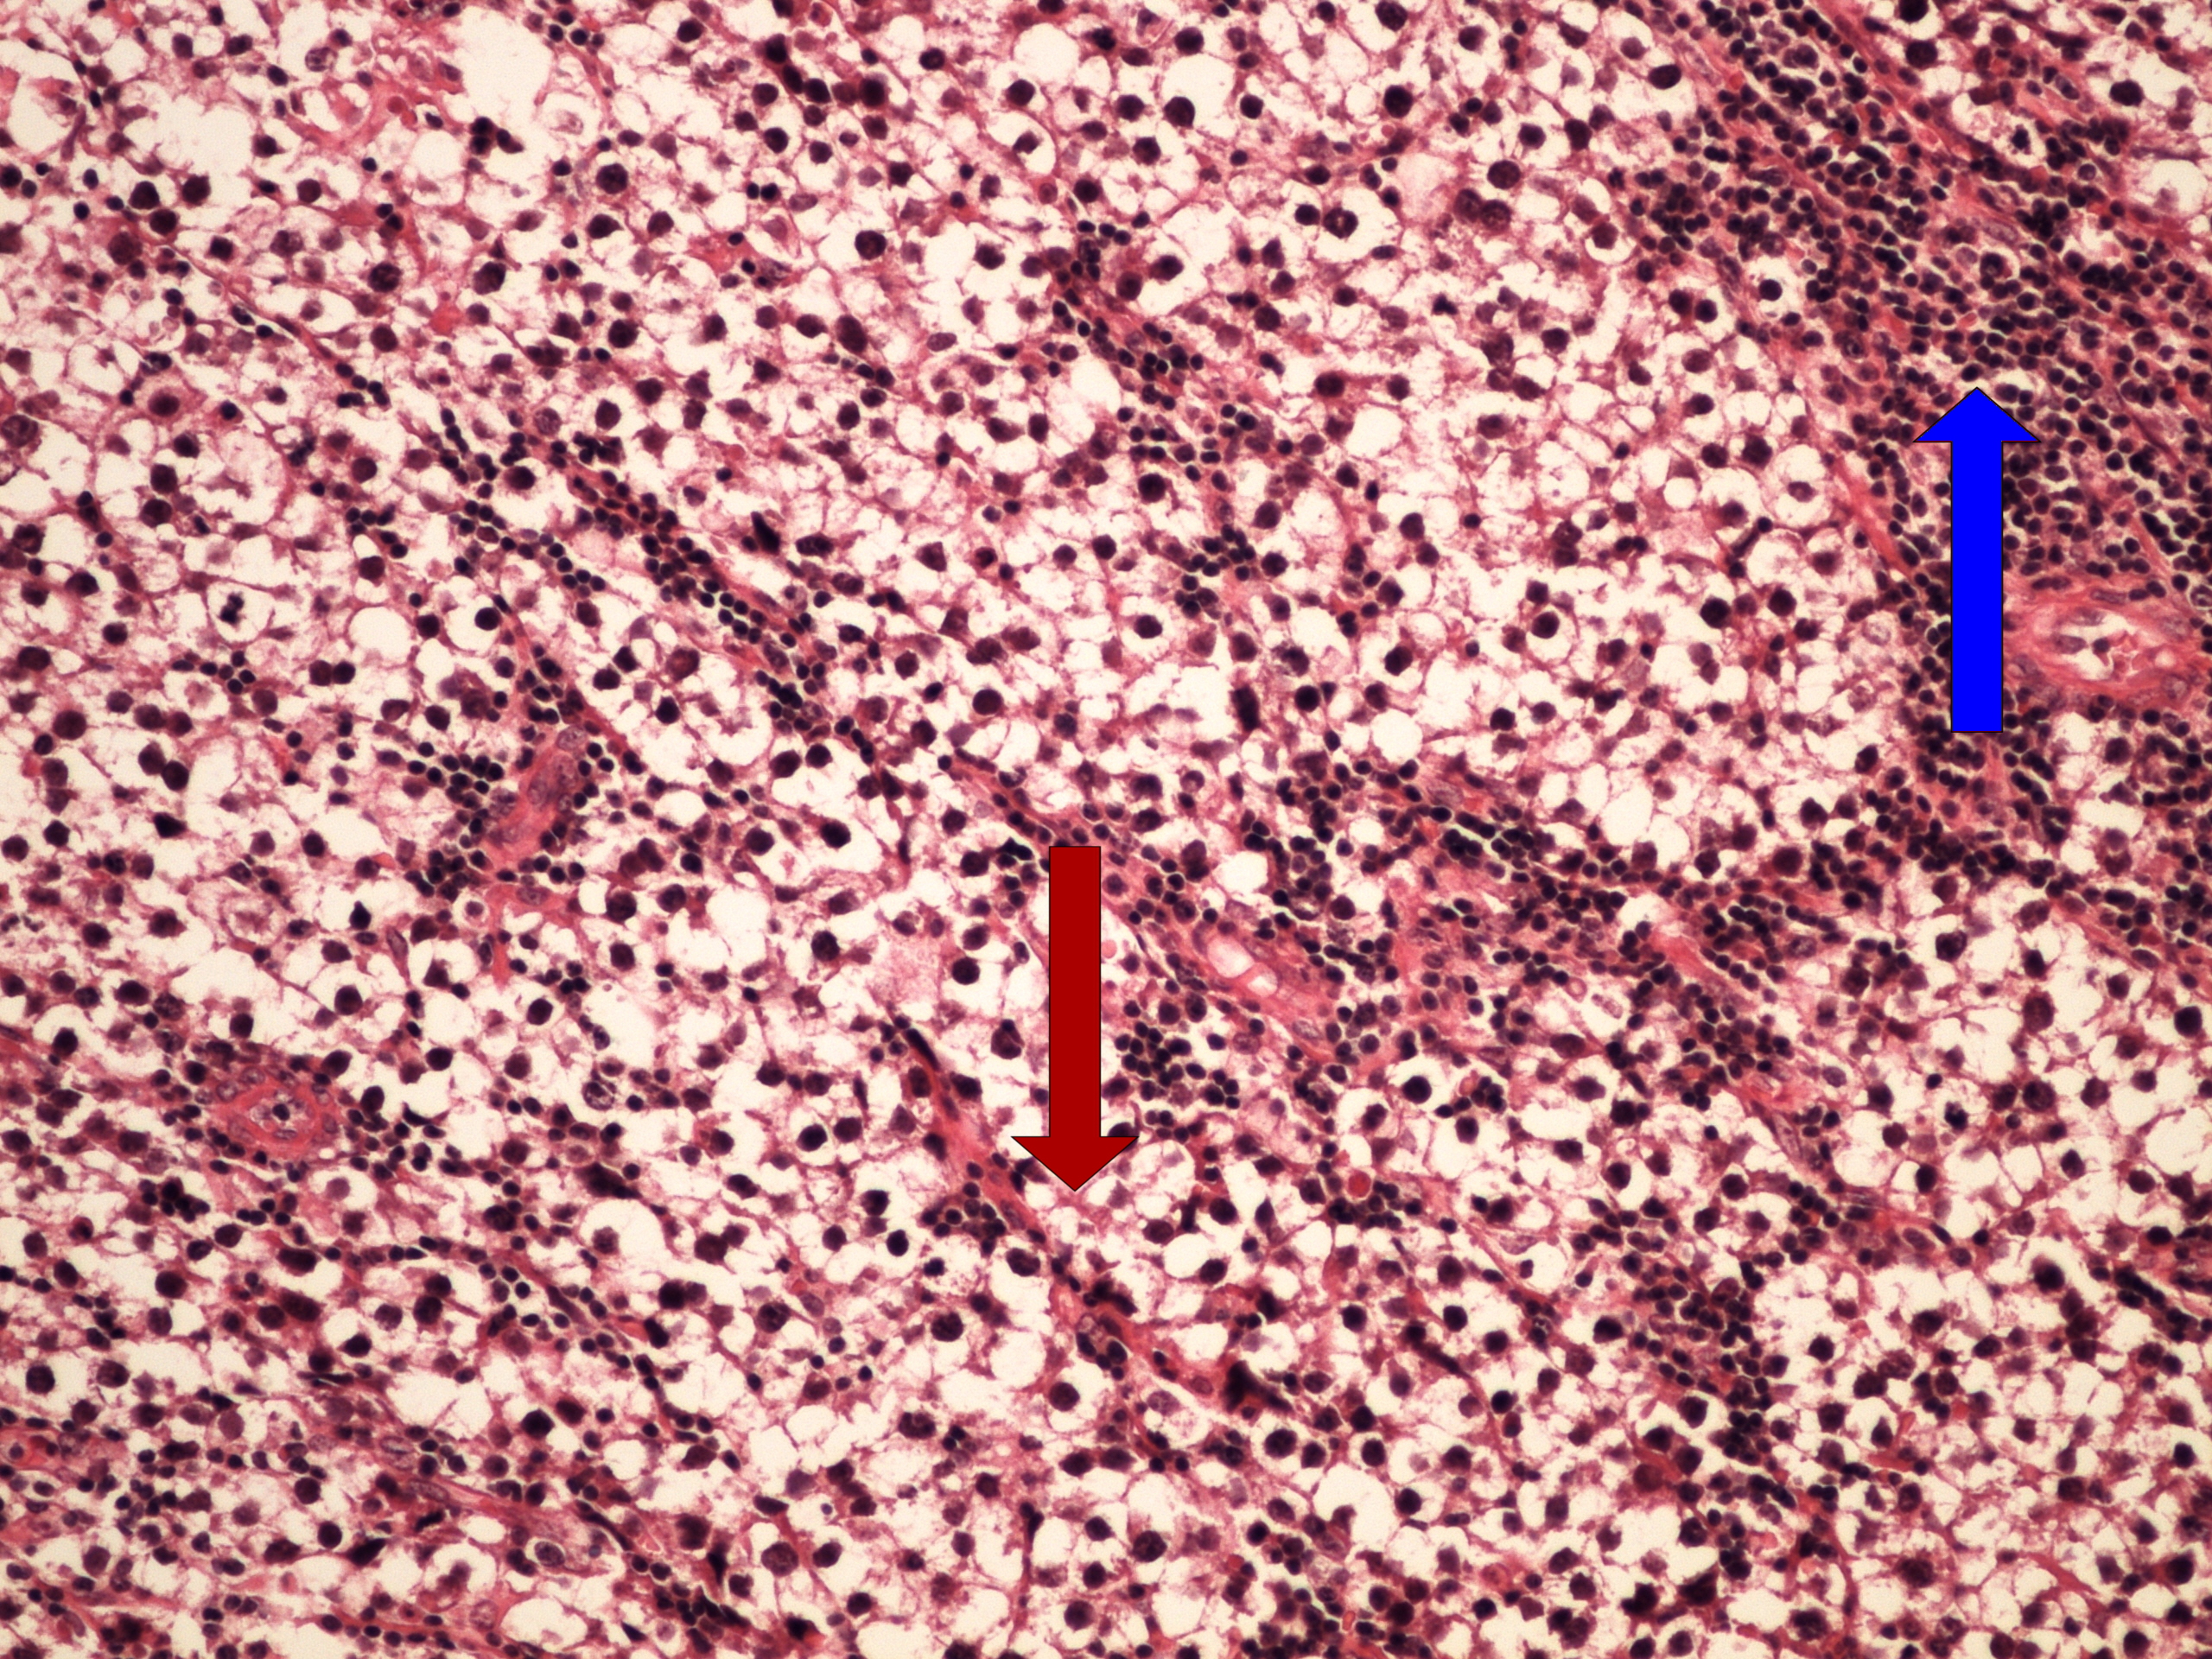

Preparát č.11 a č.12 – seminom

Struktury

- kanálky varlete

- tumor

- světlé nádorové buňky

- lymfocyty ve stromatu